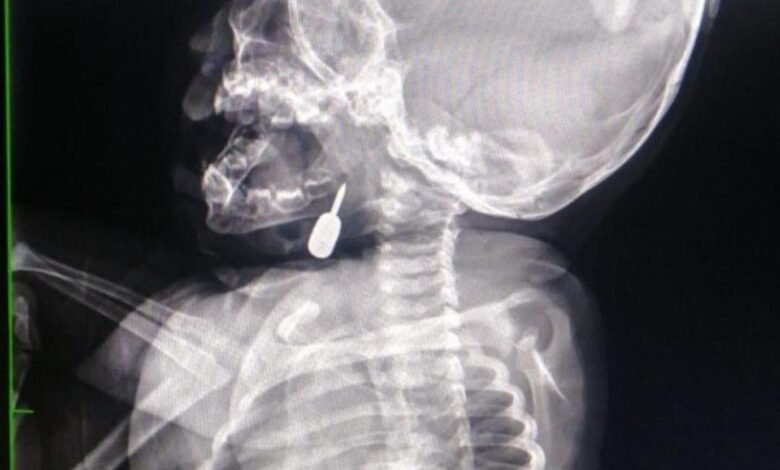

تمكّن أخصائي الأنف والأذن والحنجرة الدكتور محمود السبول من إجراء عملية فتح رغامى تعد الأولى من نوعها في مستشفى الملكة رانيا العبدالله، وقد تمت بنجاح.

وفي تدخل طبي عاجل، أنقذ الدكتور السبول حياة طفل يبلغ من العمر أحد عشر شهراً، بعد أن وصل إلى قسم الطوارئ وهو يعاني من حالة اختناق حادة نتيجة وجود جسم معدني عالق في منطقة الحنجرة. وقد تم استخراج الجسم بنجاح، مما أسهم في إنقاذ حياة الطفل.